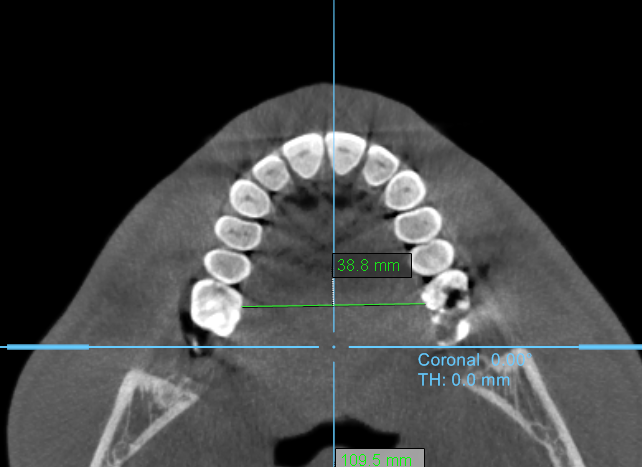

1. Palate Shape and Width

The palate appears relatively narrow and high-arched, forming more of a V-shaped rather than a broad U-shaped curve. This configuration suggests transverse constriction of the upper jaw (maxilla), particularly in the posterior region behind the first molars. A deeper palatal vault like this often corresponds to reduced nasal floor width and limited tongue space, which can influence breathing patterns and oral posture.

Overall, the palate’s form and proportions suggest a mild to moderate skeletal constriction, which could influence both dental crowding and airway size.

1. Palate Shape and Width

The palate appears relatively narrow and high-arched, forming more of a V-shaped rather than a broad U-shaped curve. This configuration suggests transverse constriction of the upper jaw (maxilla), particularly in the posterior region behind the first molars. A deeper palatal vault like this often corresponds to reduced nasal floor width and limited tongue space, which can influence breathing patterns and oral posture.

Overall, the palate’s form and proportions suggest a mild to moderate skeletal constriction, which could influence both dental crowding and airway size.